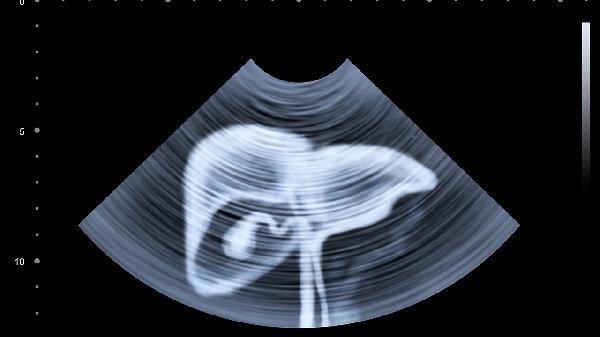

粪便嵌顿可能引发不完全性梗阻,绞痛呈阵发性加剧伴呕吐、停止排气。腹部X线可见液气平面,需禁食并急诊处理,轻症可用甘油灌肠剂通便,重症需手术解除梗阻。

女性盆腔炎或子宫内膜异位症可能因憋便压迫病灶引发牵涉痛,常伴月经异常。妇科检查及超声可鉴别,需针对原发病治疗,如使用盐酸左氧氟沙星胶囊抗感染或地诺孕素片抑制内膜增生。